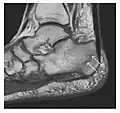

Figure 10: Calcaneal fatigue fracture in a 30-year-old male runner. Radiographs were normal (not shown). (a) Sagittal T1-weighted and (b) short tau inversion recovery images show a linear hypointensity (arrows) of calcaneal tuberosity within diffuse bone marrow edema, which appears as an ill-defined area of hyperintensity on a fluid sensitive pulse sequence (arrowheads).[1]